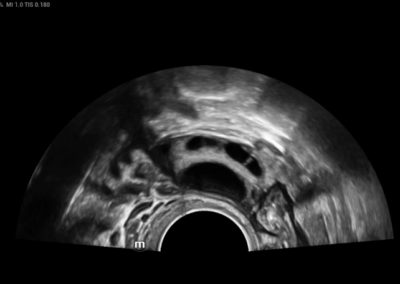

RESONA i9

Resona I9 es un sistema de ecografía de aplicación general con características notablemente innovadoras. Estas innovaciones se desarrollan sobre la base de conocimientos profundos en situaciones clínicas complejas, para proporcionar respuestas precisas y oportunas, una gran eficiencia y una notable experiencia de usuario.

Se puede ajustar para utlizar mejor el espacio

Satisface fácilmente las distintas necesidades de exploración

- Diseño del panel de control inteligente y específico para exámenes clínicos con teclas especiales de tinta electrónica

- Diseño innovador y adaptable para diferentes situaciones clínicas